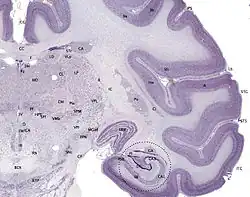

![]() |

Используется в микробиологии для гистологических, бактериологических и ботанических исследований[1].

Пригоден для витального окрашивания крови, а также нервной и опухолевых тканей.